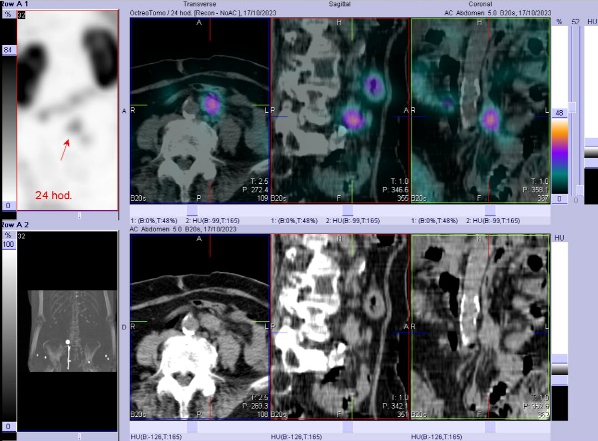

/ Obr. č. 6: Fúze SPECT/CT břicha a pánve 24 hod. po aplikaci OctreoScanu. Zaměřeno na lymfatickou uzlinu.

/ Obr. č. 7: Fúze SPECT/CT břicha a pánve 24 hod. po aplikaci OctreoScanu. Zaměřeno na lymfatickou uzlinu.